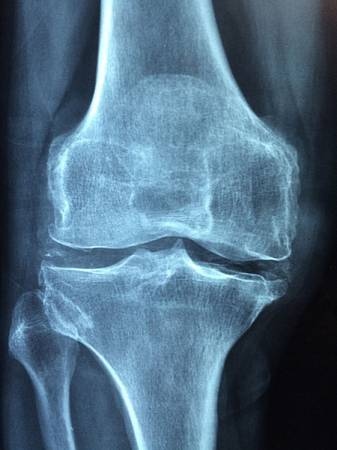

Radiografía de rodilla. (Foto: UN)